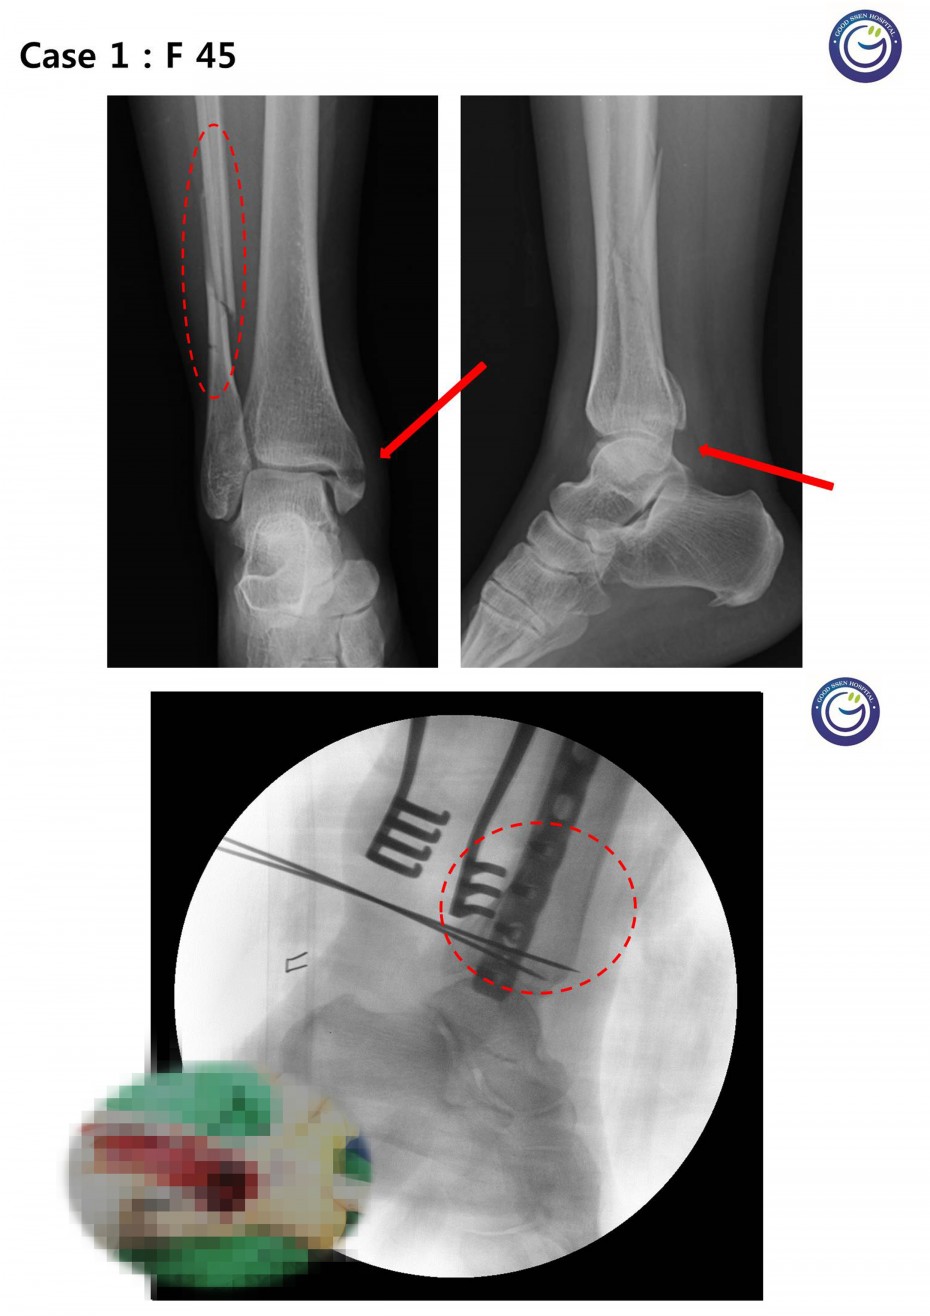

관절을 침범하는 심한 분쇄골절

절개없이 고정하는 최소침습적 고정방법 (MIPO)